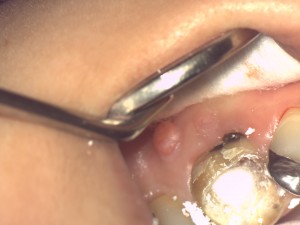

早速、仮封材(次の根管治療までの期間、歯の内部・根管を消毒し外部から細菌や唾液が内部に侵入しないように歯に蓋をする材料)を除去しようとすると、いとも簡単に除去することが出来ました。

これはいけません。歯の中に細菌・唾液が侵入して根管内を消毒、無菌的にするという根管治療の目的が達成出来ません。